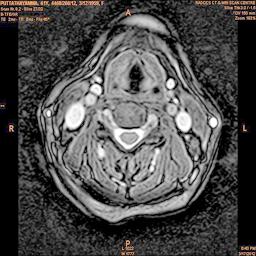

The developed algorithm presented in the previous section was coded using Matlab Version 8.0. The experiment was conducted by considering poor quality spinal cord images of having various lesions. The first column of Fig. 4 shows the axial view of neck spinal cord images of size pixels, respectively. The second column of Fig. 4 presents the same images enhanced using histogram equalization. As is evident from the results presented, the histogram equalization method performs global image enhancement operation which improves the contrast of an image but at the cost loss in image details. The third column of Fig. 4 shows the MSR based spinal cord image enhancement. It can be seen that from the result presented, MSR scheme improves the details that are not clearly visible in histogram equalization technique. In general, image enhancement achieved by MSR method is better compared to histogram equalization. However, the MSR method voilates gray world assumption. Therefore, the image enhanced by this scheme appears to be grayish. Although, numerous work have been reported for solving the problem due to gray world voilation, no work seems to developed for complete elimination.

The fourth column of Fig. 4 shows the image enhanced using Chao et al. []. It can be seen from the results presented that the reconstructed images of Chao’s method have black spots. The appearance of these dark patches degrades the visual quality of the enhanced image. The image enhanced using proposed multirate multiscale retinex image enhancement method presented in the fifth column of Fig. 4, overcomes the drawback of the Chao’s method. As we can see from the simulation results, image enhancement achieved by the proposed method has improved details with significant contrast enhancement. The enhanced images from the proposed method provides information to physicians, radiologists and researchers for various types of pathology detection.